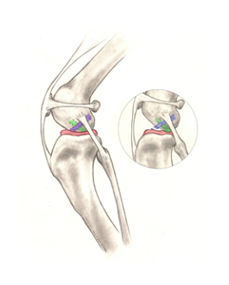

½½°³°ñ Å»±¸